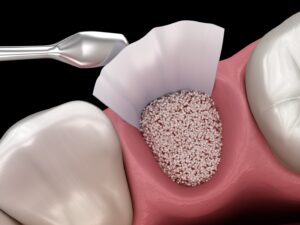

• Osspore CAS BONE VOID FILLER especially developed for regeneration of alveolar bone fallowing periodontitis.

The material is placed into the bone void under visual inspection or under radiographic monitoring during open or percutaneous surgery.

The paste may be injected into the defect, moulded by hand and digitally placed into the defect, or used to prepare beads that are placed into the defect.